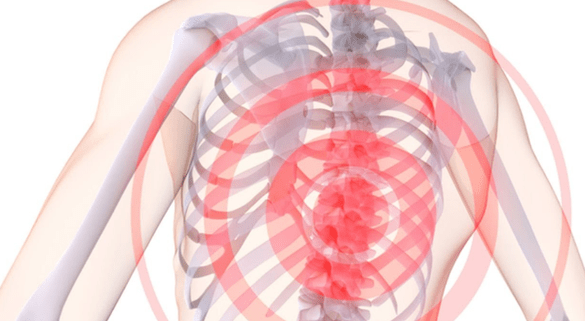

Hvad er symptomerne på thorax osteochondrose? Først og fremmest i forekomsten af smerte, som inkluderer:

- interscapular og intercostal neuralgisk lumbago;

- smerter i venstre side af brystet;

- smerter i hænderne, der forstærkes, når de løftes og når helt ud til fingerspidserne;

- smerte ved bøjning;

Derudover kan thorax osteochondrose udtrykkes i følelsesløshed - ikke kun i brystet, men også i forskellige dele af kroppen. Nogle gange fører osteochondrose til taleforstyrrelser, og nogle gange forårsager endda skællet hud, skøre negle, kløende hud og fordøjelsesforstyrrelser.

Smerter med osteochondrose i brystet kan manifestere sig på forskellige måder. Nogle gange er der tale om milde stikkende eller kedelige smerter, der viser sig sidst på eftermiddagen og forsvinder efter fysisk aktivitet – for eksempel en kort gåtur. Dette er normalt, hvordan den indledende fase af thorax osteochondrose forløber, når de intervertebrale diske endnu ikke er dybt påvirket.

I de senere stadier af udviklingen af sygdommen viser smertesymptomer sig ofte i form af lumbago. Smerten er udtalt, akut, forstyrrer normal vejrtrækning, og unødvendige bevægelser forværrer kun situationen. Ofte begynder lumbago efter en længere periode med inaktivitet - for eksempel flere timers arbejde ved en computer i en statisk stilling.